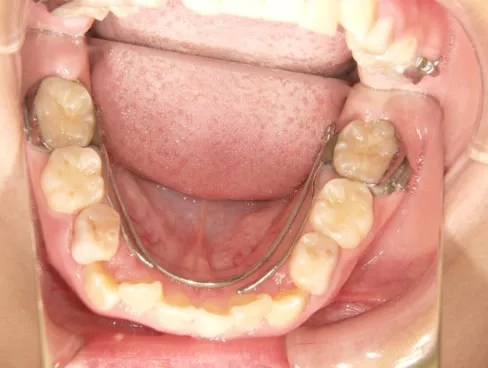

治療スタート:8y2m QH・BHで拡大、前歯の並び替えスタート

BH